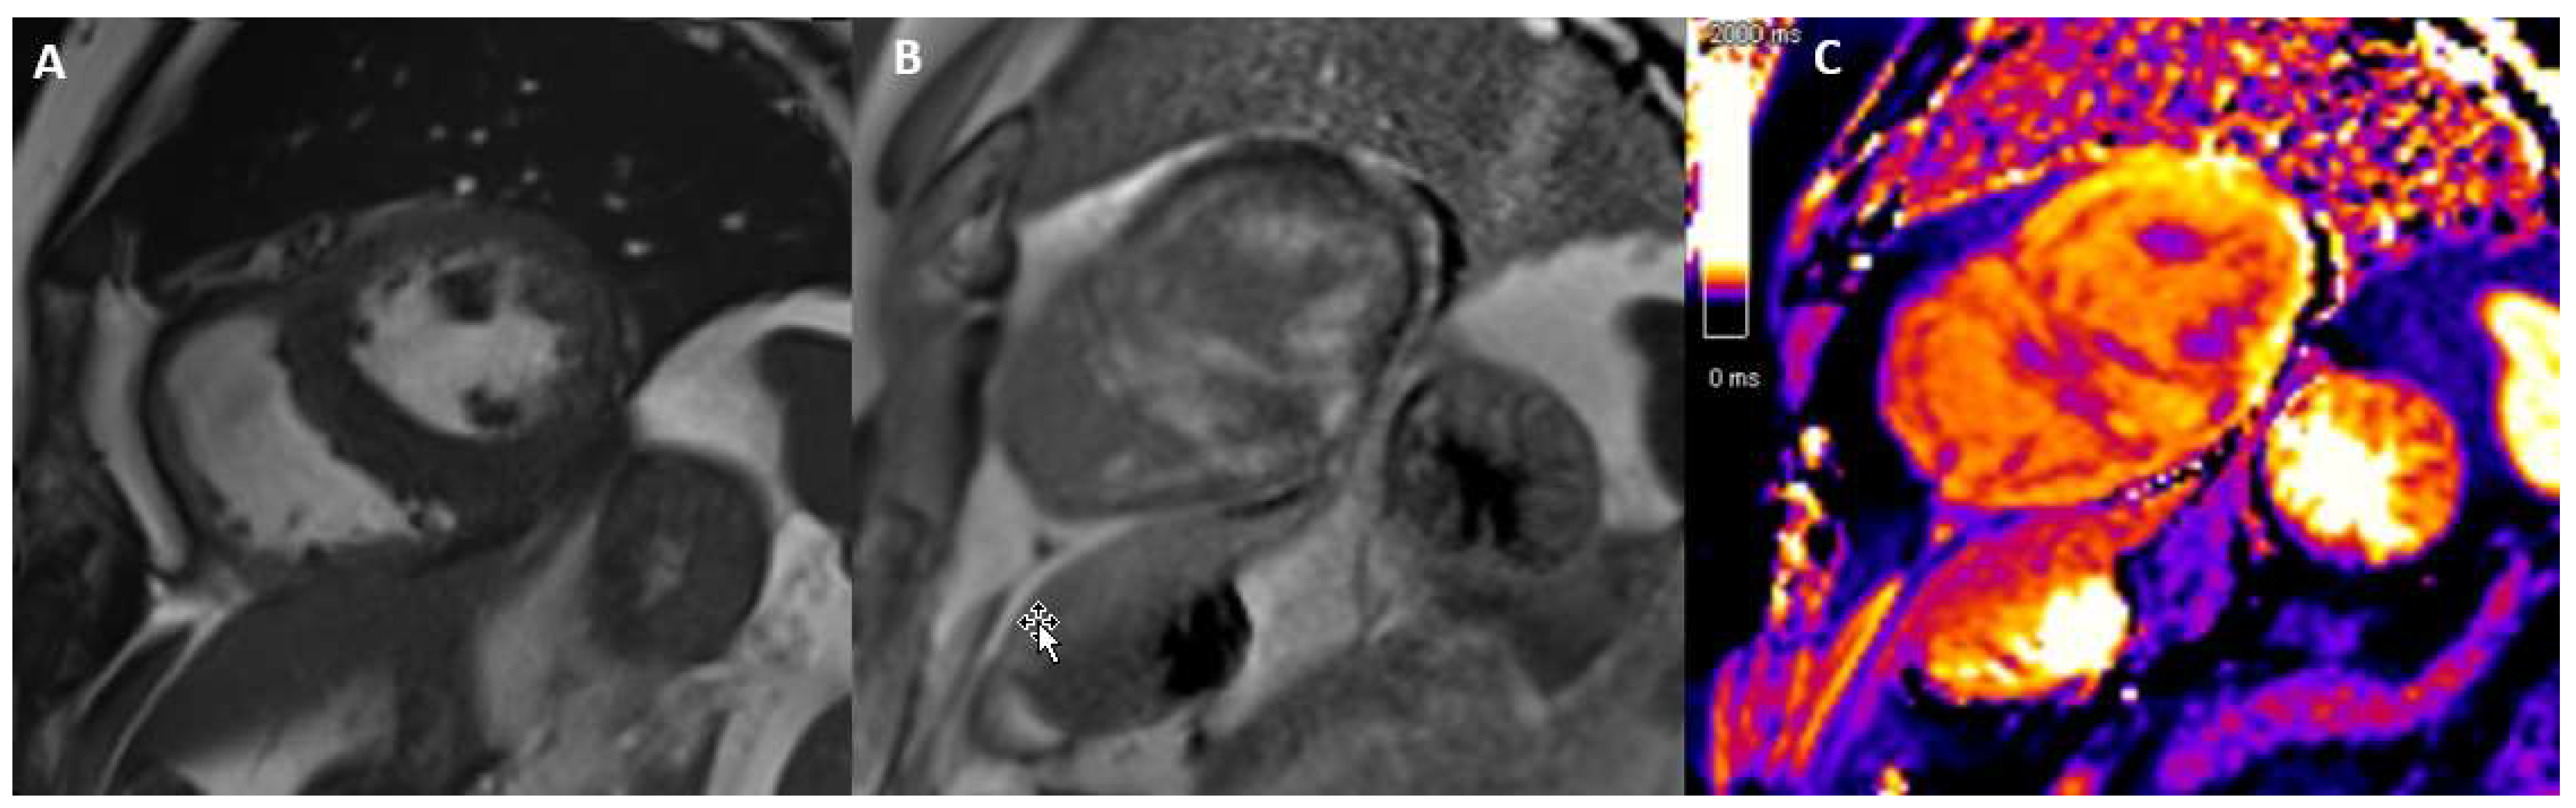

3.8. Iron-Induced Cardiomyopathy

3.9. Arrhythmogenic Cardiomyopathy